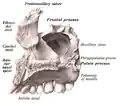

У человека воздухоносная, так как в ней находится обширная полость — верхнечелюстная (гайморова) пазуха (sinus maxillaris). Имеет тело верхней челюсти (corpus maxillae), 4 отростка: лобный отросток (processus frontalis), альвеолярный отросток (processus alveolaris), небный отросток (processus palatinus), скуловой отросток (processus zygomaticus). Поверхности верхней челюсти: передняя поверхность (facies anterior), носовая поверхность (facies nasalis), подвисочная поверхность (facies infratemporalis), глазничная поверхность (facies orbitalis)[1].

Строение верхней челюсти[2]

- тело верхней челюсти (corpus maxillae);

- передняя поверхность тела (facies anterior);

- задняя поверхность тела (facies posterior);

- глазничная поверхность тела (образует нижнюю стенку глазной впадины) (facies orbitalis);

- подглазничная борозда (sulcus infraorbitalis);

- подглазничный канал (canalis infraorbitalis);

- подглазничное отверстие (foramen infraorbitalis);

- апертура пазухи верхней челюсти, или апертура гайморовой пазухи (apertura sinus maxillae);

- альвеолярный отросток (processus alveolaris);

- альвеолярная дуга (arcus alveolaris);

- зубные альвеолы (alveoli dentales);

- межальвеолярные перегородки (septa interalveolaria);

- альвеолярные возвышения (juga alveolaria);

- скуловой отросток (processus zygomaticus);

- лобный отросток (processus frontalis);

- слезная борозда (sulcus larcimalis);

- носовой гребень (crista conchalis);

- решетчатый гребень (crista ethmoidalis);

- подглазничное отверстие (foramen infraorbitale);

- небный отросток (processus patalinum);

- носовая передняя ость (spina nasalis anterior);

- носовой гребень (crista nasalis);

- небные борозны (sulci palatinae);

- небные ости (spinae palatinae);

- резцовый шов (sutura incisiva);

- резцовая ямка (fossa incisiva);

- резцовое отверстие (foramen incisiva);

- срединный небный шов (sutura palatina mediana).